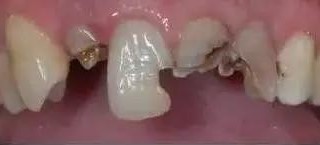

蛀牙是形成“烂牙根”的主要原因,对口腔卫生不重视,容易造成口腔细菌滋生,由刚开始的“小黑点”到形成浅浅的龋洞。若放任不管,牙齿龋坏继续发展,之后牙神经坏死、牙齿变脆、牙体硬组织就会逐渐脱落,慢慢仅剩下残根!这时,再不理不睬,“烂牙根”会引发大问题!